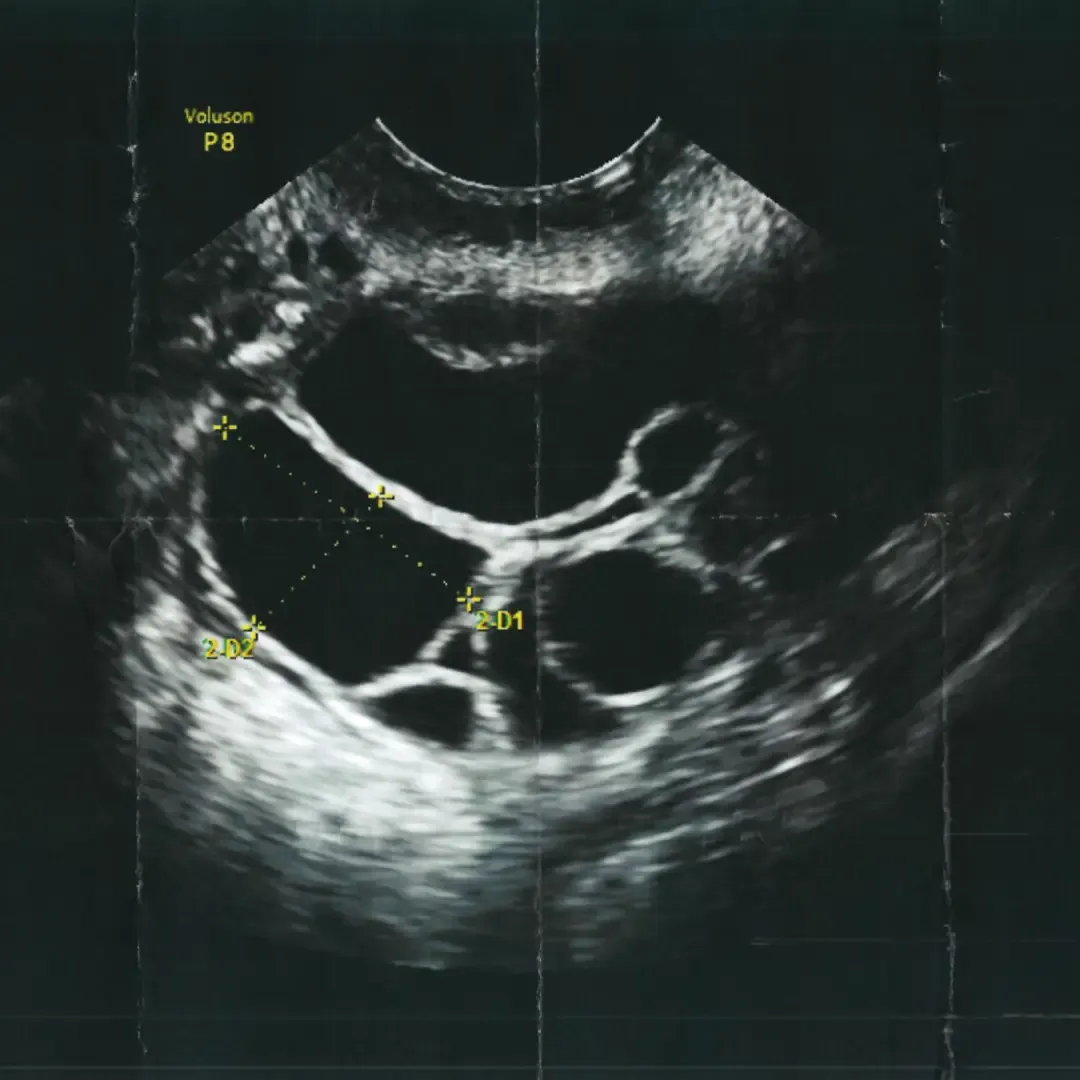

The TFP Fertility journey began when Professor Fleming’s team demonstrated how ultrasound scan can be used to identify and measure follicular growth.

This was pivotal for the fertility sector, enabling doctors to assess follicular development during an IVF cycle. Treatment became far less invasive for the patient, particularly during egg collection, allowing doctors to direct the needle into the follicle to retrieve the egg rather than performing a laparoscopy under general anaesthetic, minimising the risk to the patient.

Through the evolution of technology, ultrasound has become more sophisticated and precise, providing better images and resolution. Because of this, ultrasound can now be used to:

Predict how a person may respond to treatment by counting the follicles in their ovaries

Identify underlying issues that may prevent an embryo from implanting

Perform embryo transfers with greater precision, ensuring the embryo is transferred safely and quickly